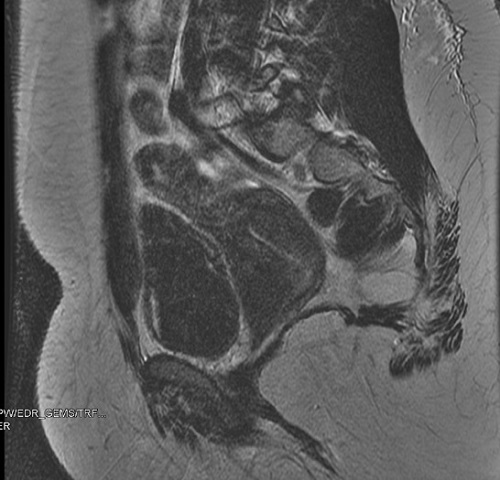

Se indica tomografía computarizada urgente en el que se visualiza útero con marcada distensión del cuerpo, en probable relación con malformación vaginal y riñón derecho único (Fig. 1).

Figura 1. Tomografía computarizada